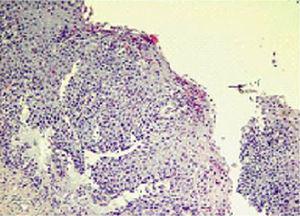

Presentamos el caso de un varón de 11 años de edad con EE de 7 años de evolución. El estudio consistió en la realización de pH-metría, con resultado normal, endoscopia digestiva alta con toma de biopsias que confirmó el diagnóstico (Figura 1) y un estudio alergológico completo para alimentos y aeroalérgenos. Desde el inicio del cuadro, nuestro paciente no experimentó mejoría clínica ni endoscópica a pesar de recibir varios tratamientos: dieta de exclusión de alimentos sospechosos, inhibidores de la bomba de protones, montelukast, terapia nutricional con dieta elemental y corticoides tópicos (propionato de fluticasona deglutida). Se intentó terapia con corticoides sistémicos, suspendiéndose por aparición de efectos adversos. Sólo se consiguió mejoría clínica tras iniciar terapia con dieta elemental exclusiva durante 8 semanas, pero al introducir de nuevo la alimentación reaparecieron la sintomatología y la alteración endoscópica.

Figura 1. Anatomía patológica de mucosa esofágica: aumento de papilas e hiperplasia de células basales. Infiltrado de eosinófilos > 50-60/campo.